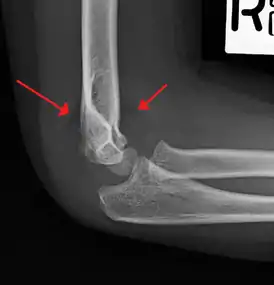

Fat pad sign/sail sign - A non-displaced fracture can be difficult to identify and a fracture line may not be visible on the X-rays. However, the presence of a joint effusion is helpful in identifying a non-displaced fracture. Bleeding from the fracture expands the joint capsule and is visualized on the lateral view as a darker area anteriorly and posteriorly, and is known as the sail sign.[8]

Fish-tail sign - The distal fragment is rotated away from the proximal fragment, thus the sharp ends of the proximal fragment looks like a shape of a fish-tail.[8]